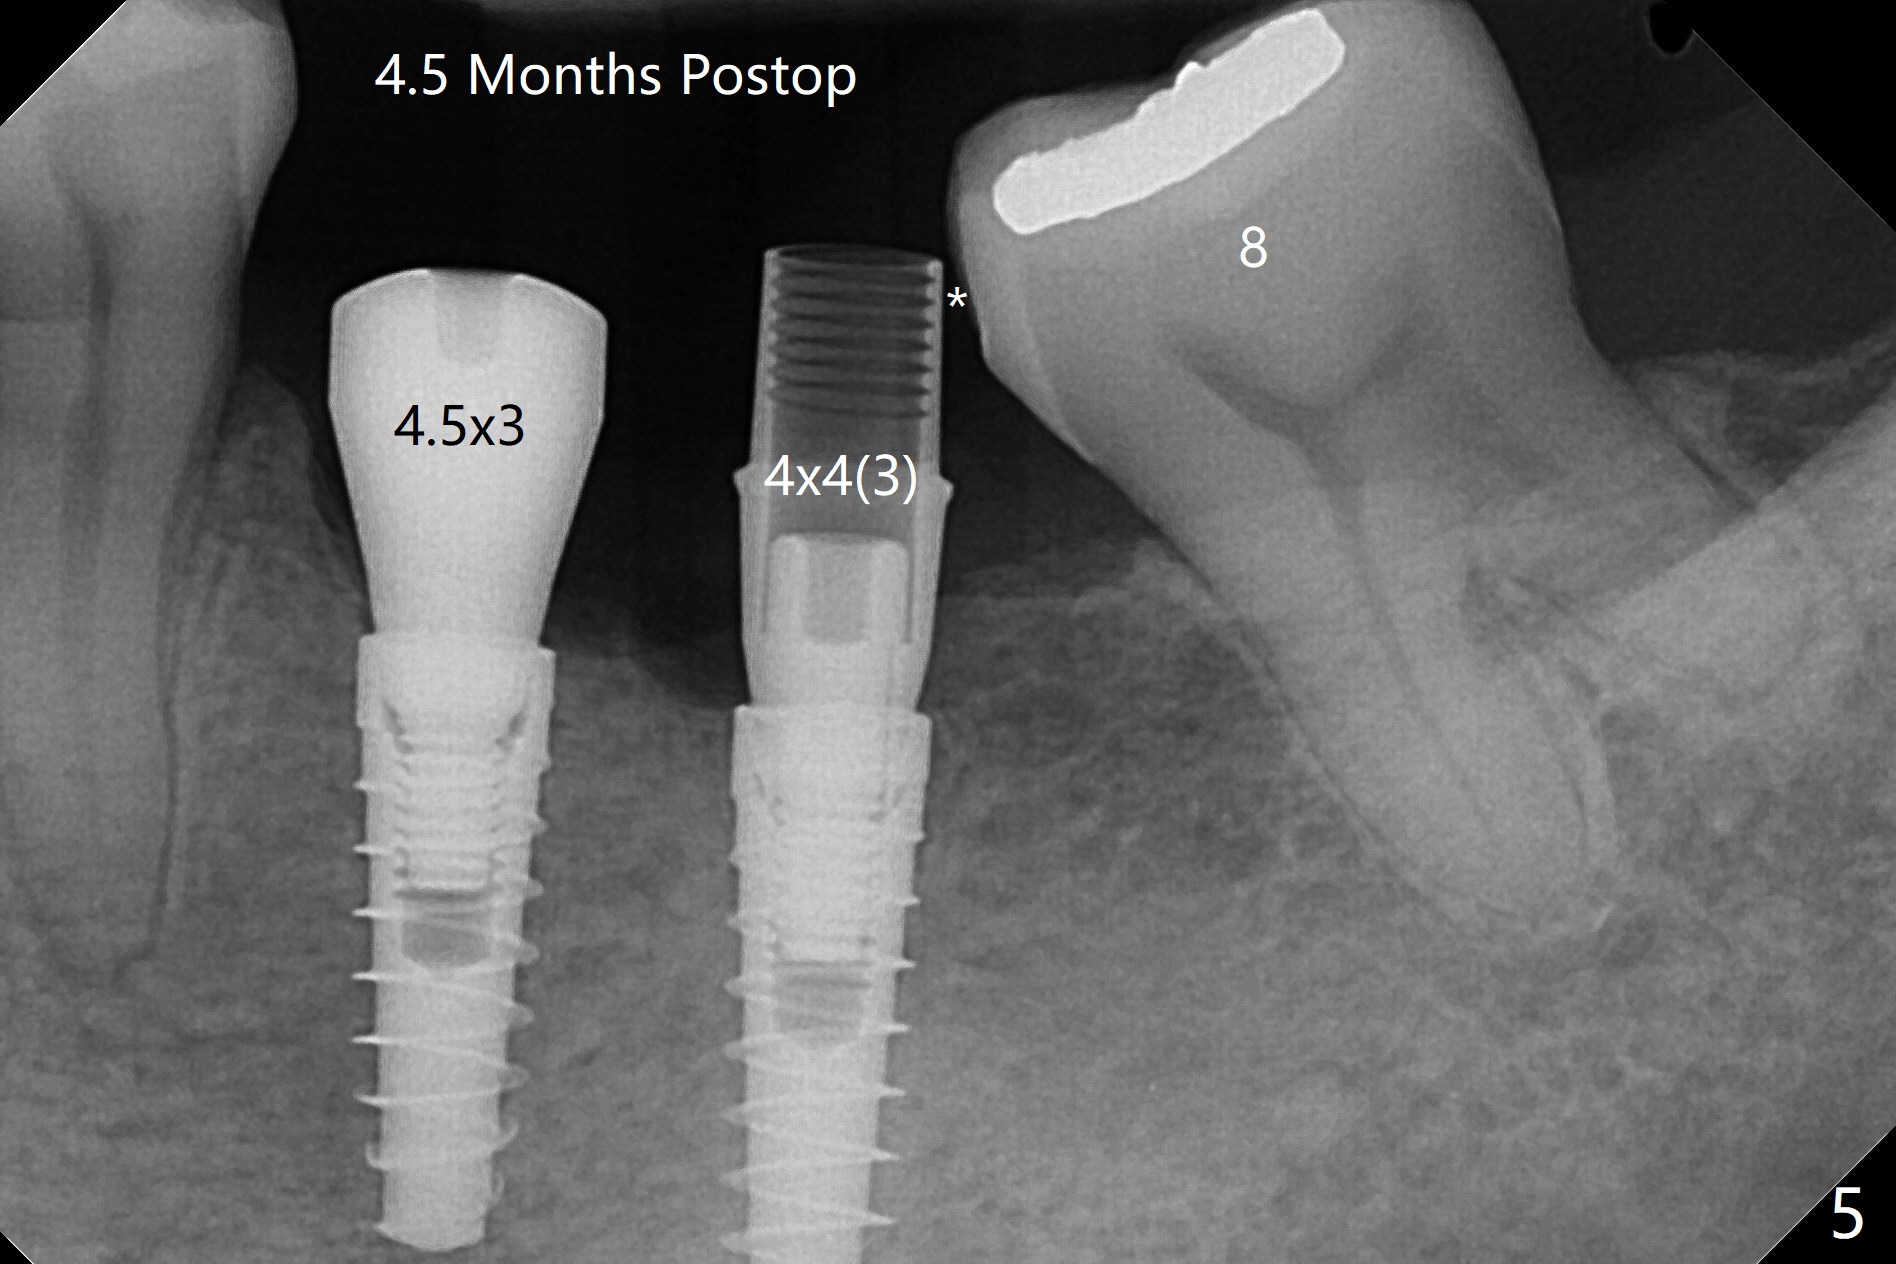

左下6,7导板设计种植两个小植体,牙槽嵴角化龈狭窄(图一:*),切开,钻洞,6处骨质密度高,钻头与植体直径必须一样,但是为了保证稳定性,最后1.5毫米钻头小0.5毫米,植体最后1-2毫米必须倒旋一次才能控制扭力不超过40Ncm,术后即刻根尖片显示4,6根尖部(密度2200单位,图二)螺纹弯曲(<),而7(密度670单位)钻头比植体小0.5毫米,植入扭力也大约40Ncm,不过螺纹没有变形。祸不单行,6植体冠部舌侧螺纹暴露约1毫米,放入自体骨后,盖膜(6个月),4-0铬羊肠线减张缝合(图三),牙槽嵴好像增宽了。术后两周伤口愈合(图四)。术后4.5个月切开暴露,尽管需要外科钻头去除植体冠部骨质,6舌侧植体螺纹仍暴露,放置4.5x3毫米愈合基台,7放置4x4(3)毫米修复基台(图五),但是接近8牙冠,无法修复,必须做局部牙齿矫正。术后7个月7放置3.4x3毫米愈合帽,6放置4.5x5.7(4)毫米修复基台,手拧紧,做临时牙冠,垫高,开始矫正;一个月后基台松动,扳手拧紧(30Ncm);7处3.4x3毫米愈合帽没有就位,由于远中牙槽嵴阻挡(图六:<)。